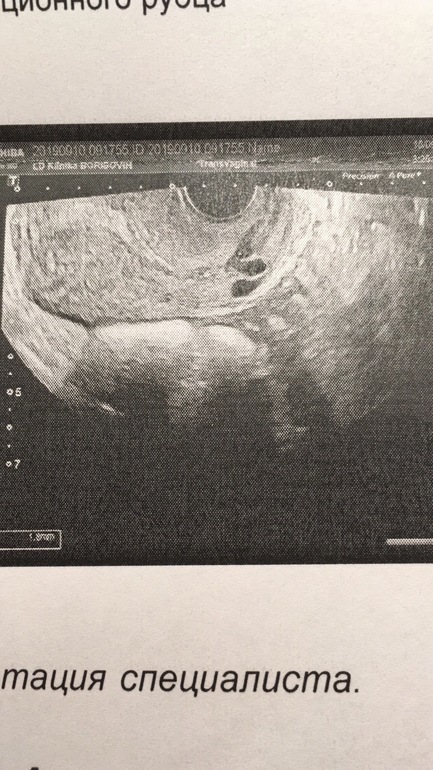

Отсутствие эмбриона

Подозрение на двойню не оправдалось (ну и ладно), но беспокоит другое. Сегодня делала узи и эмбриона не обнаружили... Размер ПЯ уже 10,6 мм, желточный мешок 3,9 мм. По месячным срок - ровно 6 недель. Если судить по поздней овуляции - акушерский срок 5 не...